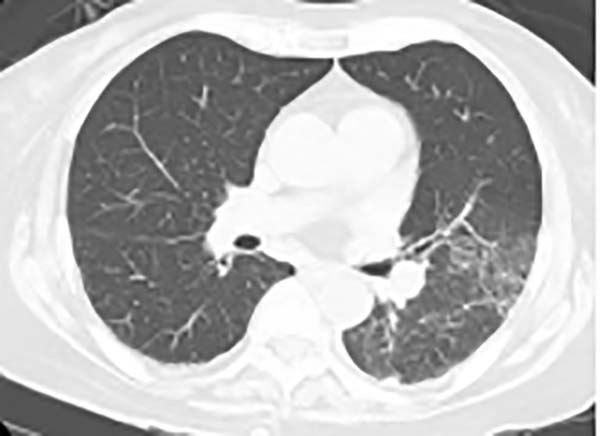

三、胸CT有哪些特点?

胸CT以炎性病变始于单侧肺下叶多见,加重后累及双侧肺叶,上下肺均可受累,主要表现为大片状实变影,可合并小片状磨玻璃影、结节影,以胸膜下分布为主,可见“支气管充气征”“细网格征”“晕征”,常伴胸腔积液,可伴淋巴结肿大。